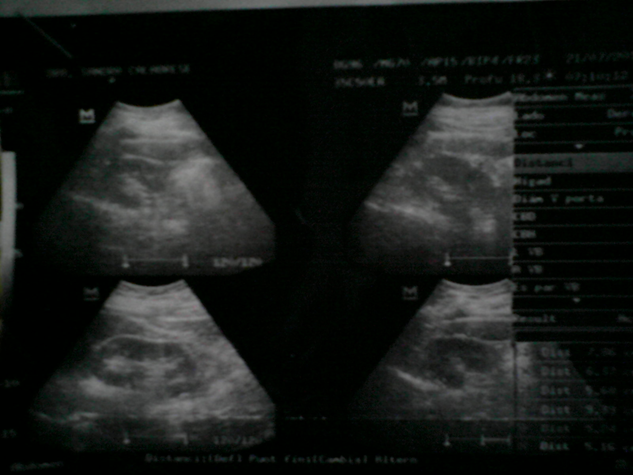

Diagnóstico

Para realizar un diagnóstico definitivo de litiasis renal es necesario confirmar la presencia de la misma, así como también es importante detectar las complicaciones que pueden estar asociadas y por ultimo como en todo diagnóstico es fundamental hallar la causa de la enfermedad y de esta manera indicar un tratamiento oportuno y especifico. Para lograr el objetivo se debe realiza una correcta anamnesis (inicio de la enfermedad, frecuencia, si ha tenido intervención urológicas, infecciones urinarias recurrentes, antecedentes familiares, tipo de alimentación, administración de fármacos, si existe alguna enfermedad(es) de base, entre otras). Sumado a esto también ha de realizarse una exploración física completa y precisar pruebas complementarias.

Pruebas Complementarias